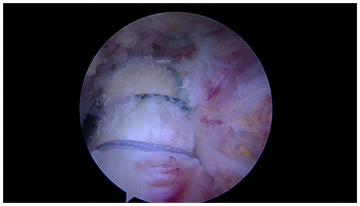

Anchor Bounded hybrid Repair (Figure 4): This technique prioritizes anchors as the primary means of fixation, and allows for the repair of any sized cuff tear with a transosseous equivalent four anchor construct. This repair is typically applied in severely retracted tears, reconstructions, or tears with noncompliant tissue. Anchors are placed at the margins of the tear, securing the mechanically important cables of the rotator cuff, while the intervening tissue is circumferentially opposed to bone with either one or two transosseous tunnels. The tunnels between the anchors respect the biology and bone stock of the tuberosity, while adding additional circumferential compression points of the tendon footprint. Additional tunnels may be created as needed for “dog ears” or further cuff reduction. This paradigm may also be used in superior capsular or graft augmentations, as there are often edges of the graft which must be secured for stability of the graft interface, even after multiple anchors have been used (Figure 5).

Figure 4  Anchor bounded hybrid repair.